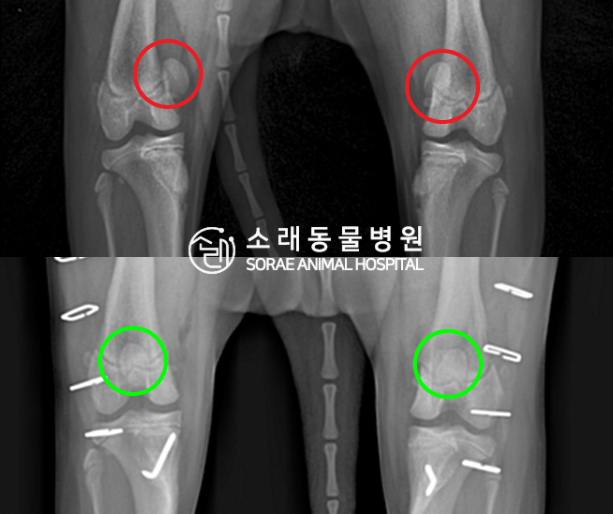

수술전과 수술후에 촬영한 쿠키의 슬개골

방사선 사진입니다. 나란히 놓고 비교해보니

슬개골의 위치에 확연한 차이가 있는 것을

확인해 볼 수 있는데요. 내측으로 탈구되어 있던

슬개골이 원래 제자리인 활차구에 예쁘게

자리 잡고 있는 모습을 확인할 수 있었습니다.